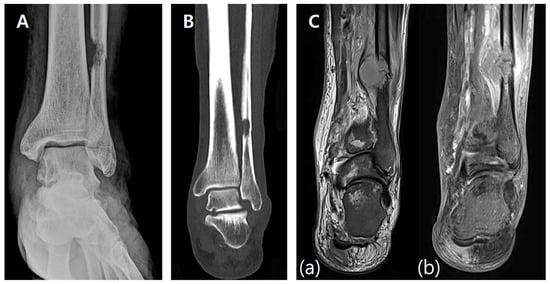

A 17-year-old female presented with a palpable mass on the medial aspect of her left foot and progressive difficulty in ambulation and daily activities. A family history of neurofibromatosis, specifically with respect to her mother, was noted. A preoperative radiographic evaluation revealed a 25 × 12 × 15 mm3 hypodense mass located in the body of the calcaneus. Plain X-ray (Figure 1A) and CT scans (Figure 1B) showed cortical thinning and a well-defined lesion within the calcaneus. MRI scans demonstrated a homogenous low signal intensity in T1-weighted images and heterogeneous high signal intensity with central low-signal areas in T2-weighted images, consistent with a benign neurogenic tumor (Figure 1C).

Figure 1. Preoperative imaging. (A) Preoperative X-ray showing a well-demarcated lesion within the calcaneus with cortical thinning and intact surrounding bone structures. (B) Preoperative CT scan demonstrating a 25 × 12 × 15 mm hypodense lesion in the calcaneal body, with thinning of the cortical bone and no evidence of periosteal reaction. (C) Preoperative MRI. (a) T1-weighted image showing homogenous low signal intensity. (b) T2-weighted image showing heterogeneous high signal intensity with central low-signal areas.